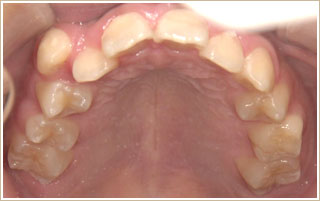

▼治療前

▼治療後

7ヶ月間で横に約4mm顎が拡がり、大体歯が並ぶスペースが出来ました。